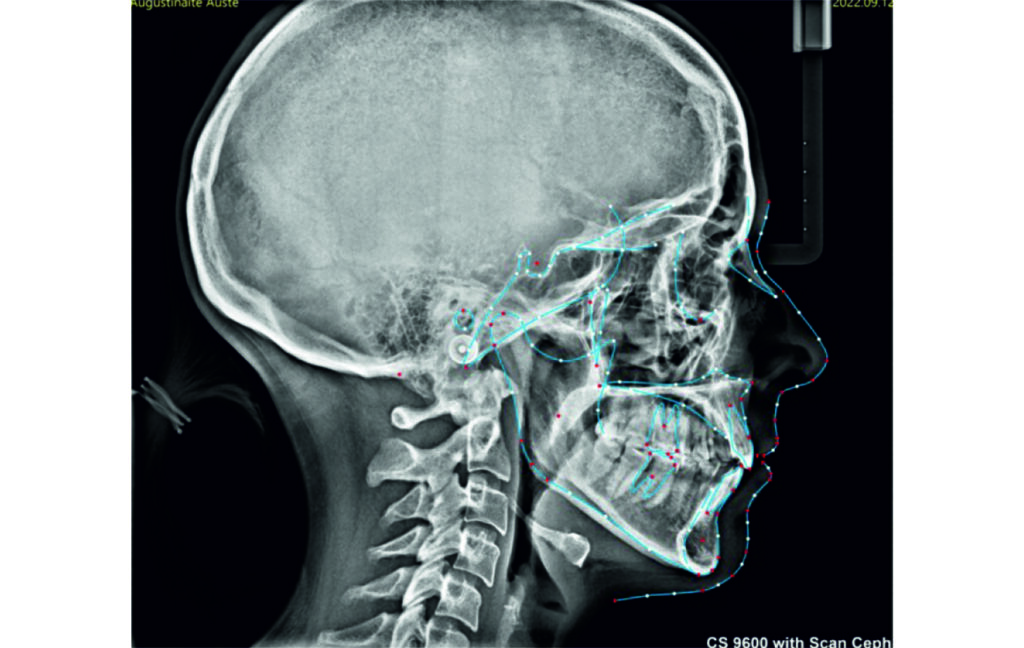

Angle Class II 2mm on the right, Angle Class II 2mm on the left, light mandibular asymmetry to the right, lower central line 1mm to the right, upper central line 1,5mm to the left, 1mm overjet and overbite. Sagittal asymmetry of upper dental arch. Light crowding upper and lower frontal segments, severe attrition of posterior teeth, night bruxism. Normal sagittal position of both jaws, high angle case, steep mandibular ramus,excessive lower facial height, open bite tendency.

Soft Tissue Analysis: convex profile, lower third of the face increased, slightly retrusive upper and lower lips, lip strain on closure.

An infrazygomatic crest (IZC) screw with force applied between the upper premolars produces a clockwise rotation of the maxillary occlusal plane. This movement aids in closing the anterior open bite and improves upper incisor display. IZC screws with elastics also enable planned intrusion of the upper molars by 1 mm. Because mandibular derotation after upper posterior correction is difficult to predict, anterior distalization and midline correction were performed in the later stages of treatment.